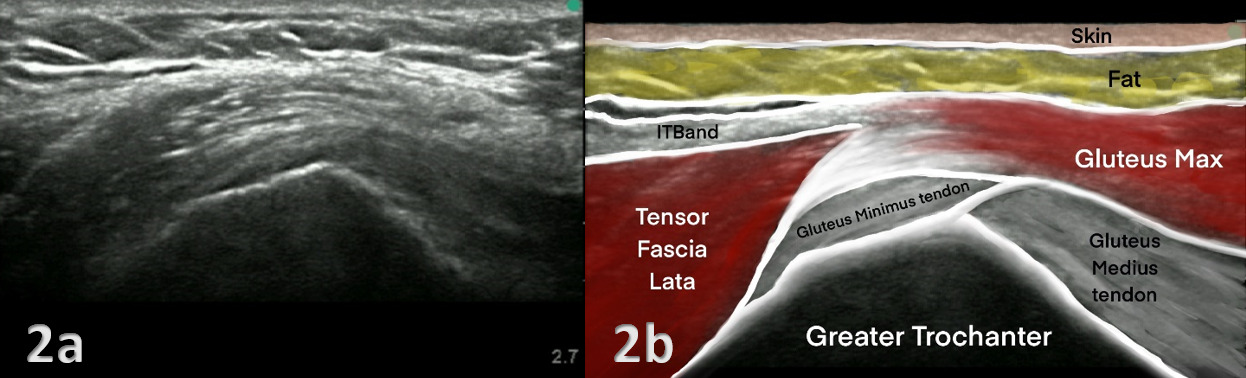

The evaluation of the gluteus medius tendon with MSKUS begins with the patient in a lateral decubitus or standing position, targeting the lateral aspect of the hip. The normal gluteus medius tendon appears as a fan shaped fibrillar structure composed of hyperechoic, striated fascicles with bright, linear bands running within the muscle.2 Pathological changes such as tendinopathy are characterized by hypoechoic (darker) regions within the tendon, tendon thickening, and loss of the normal fibrillar pattern. Tears are identified by discontinuity in the tendon fibers, with partial tears showing as anechoic (black) areas and complete tears as a full separation of the tendon from its insertion.